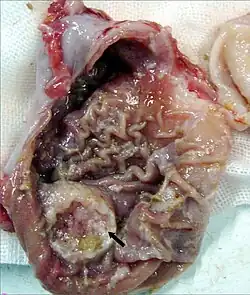

Histopathologie

Die Mehrheit der Karzinome zeigt unter dem Mikroskop Siegelringzellen. In den Zellen ist der Zellkern an den Rand gedrängt, und sie reagieren stark mit der PAS-Färbung. Seltener treten Karzinome auf, die den Drüsen des Darmes ähneln. Es sind auch Gallertkarzinome beschrieben, bei denen außerhalb der Krebszellen Massen von PAS-positivem Schleim liegen, sowie entdifferenzierte Karzinome, deren Herkunft sich nur durch immunhistochemische Methoden klären lässt. Neben diesen Tumoren, die vom Epithel des Magens ausgehen, sind auch neuroendokrine Tumoren beschrieben.[12]

Man unterscheidet je nach der Form des Tumorwachstums vier Typen von Adenokarzinomen des Magens. Das polypoide Adenokarzinom wächst wie ein Polyp von der Mageninnenseite in das Magenlumen ein. Das ulzerierende Adenokarzinom zeichnet sich durch die Bildung einer Schleimhautschädigung im Sinne eines Geschwürs aus. Gegenüber gutartigen Magengeschwüren zeigt das Karzinom unregelmäßigere Ränder. Beide Typen machen je ein Drittel der Magenkarzinome aus. Rund ein Zehntel aller Magenkarzinome sind vom diffusen Typ. Diese Tumoren wachsen nicht in das Lumen ein, sondern infiltrieren das Gewebe des Magens. Die Tumorzellen induzieren eine Fibrose in der Schleimhaut- und der Muskelschicht des Magens, was zu einer Wandverdickung führt. Der diffuse Typ ist mit einer besonders schlechten Prognose assoziiert. Als Frühkarzinom des Magens bezeichnet man einen Tumor, der auf die Schleimhaut oder die Submukosa beschränkt bleibt. Obwohl rund 20 % der Frühkarzinome bei Diagnosestellung bereits metastasiert haben, besitzen sie im Vergleich zu den anderen Arten eine relativ gute Prognose.[13]